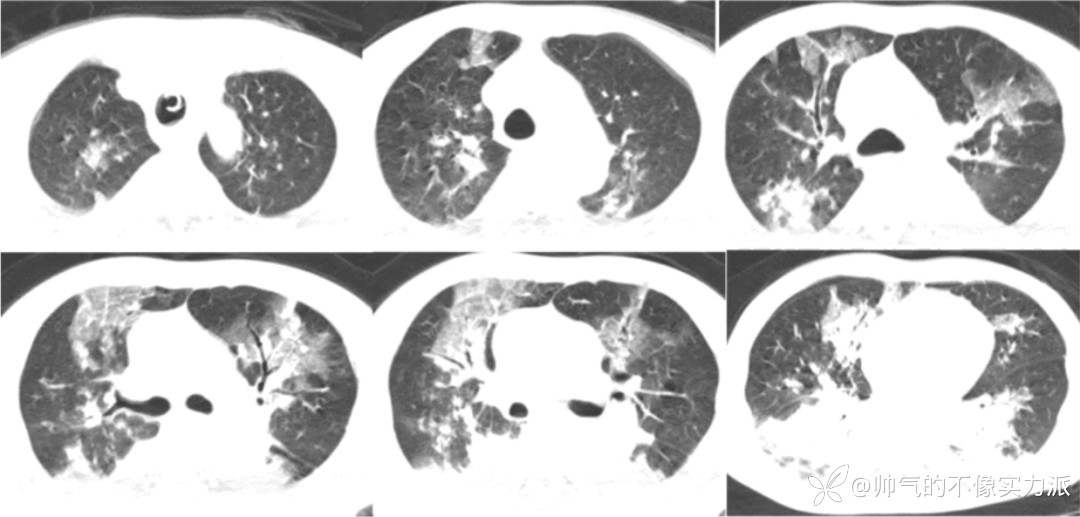

- 复查胸部CT(2020-12-16):双上肺病变仍然较重,双下肺重力依赖区实变影明显吸收,双侧少量胸腔积液(图5)。

图5 患者胸部CT(2020-12-16)

- 2020年12月23日复查胸部CT:双上肺病变明显吸收,遗留少量斑片条索影,双下肺吸收良好(图7)。

图7 患者胸部CT(2020-12-23)